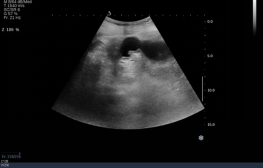

1,2  上消化道对比造影示:胃内充盈缺损影,大小约10.7x5.7cm,可随体位变化移动,考虑胃石。